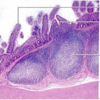

What is pictured here; what layer are they found in?

Peyer’s Patches; found in the Mucosa